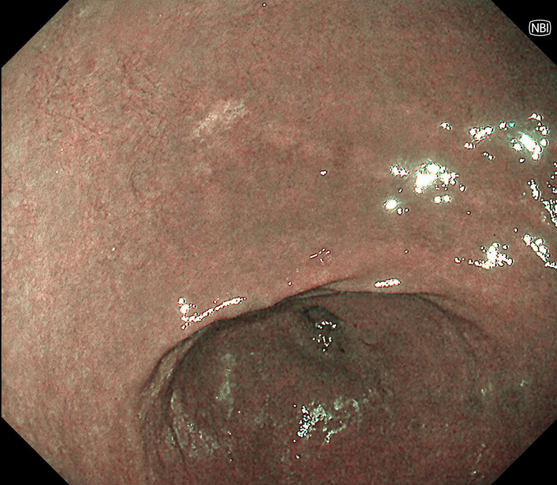

当クリニックで発見された微小胃腫瘍

①白色光像

胃体部に黄色調の平坦陥凹病変

②NBI(狭帯域光観察)併用非拡大観察

同部位に茶色様変化あり

➂NBI併用拡大観察

陥凹内に腫瘍血管を認め、腫瘍性病変と診断 病理診断: 4mm Group3 (胃腺腫)